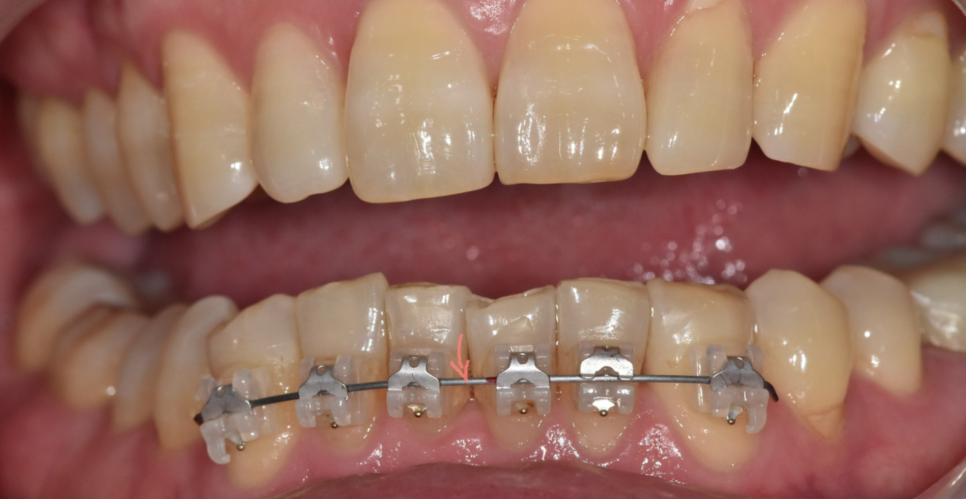

교정 초기와 후반부에 사용하는 와이어 역할이 다릅니다.

초기에 쓰는 얇은 철사는 유연하고

휘어져도 원래 모양으로 돌아가려는 성질이 강합니다.

삐뚤어진 치아를 제자리로 이동시키는 성질이 있어요

교정 중간~후기에는 굵고 단단한 철사를 사용합니다.

강한 힘을 지속적으로 주어

치아의 세밀한 정렬을 도와주죠

사용하는 와이어에 따라

치아에 전달되는 힘의 크기와 방향이 달라지기 때문에,

치료 단계에 맞는 와이어를 선택하고 바꾸는 과정이 꼭 필요합니다.